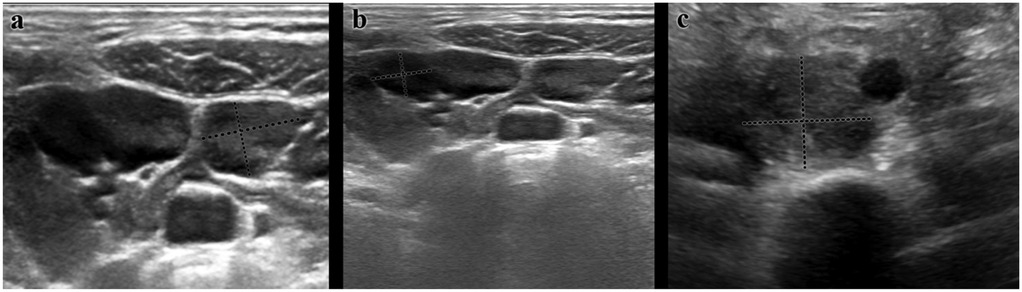

You don't have a Frontiers account ? You can register here

Pediatric lymphadenopathy is common, yet distinguishing benign from malignant causes remains challenging; objective predictors are needed to refine biopsy decisions. We retrospectively analyzed 500 children (0–18 years) with regional enlarged lymph nodes evaluated at a tertiary pediatric hematology–oncology clinic (June 2024–March 2025). Demographics, node location and size, multiplicity, ultrasonographic (US) assessment, viral tests, biopsy, and bone marrow results were extracted from the hospital system. Associations with definitive diagnosis were tested, and multivariable logistic regression identified independent predictors of malignancy. Median age was 6 years; cervical nodes were most frequent (92.2%), and multiple nodes were present in 93.6%. Biopsy was performed in 47 patients, yielding malignancy in 23 (48.9%). Final diagnoses were reactive lymphadenopathy (87.4%), hematologic malignancy (4.4%), and metastatic solid tumors (1.4%). On univariable analyses, larger size (≥2 cm), multiplicity, and certain regions were associated with malignancy (p<0.05). However, in multivariable analysis only US findings remained independently predictive: nodes categorized as suspicious on US were associated with an approximately 56-fold increase in the odds of malignancy (adjusted OR ≈55.6; 95% CI ≈14.3–200; p<0.001), whereas size and anatomical region were not significant. These data support an ultrasound-centered approach to biopsy referral in childhood lymphadenopathy, potentially reducing unnecessary invasive procedures while maintaining timely detection of malignant disease.